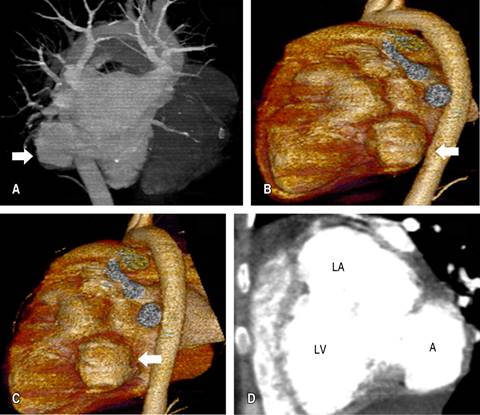

A 12-electrocardiogram was performed, showing sinus rythm but with signs of left chamber overload (Figure 1). A transthoracic echocardiogram was then requested, which revealed an image suggestive of aneurysm formation in mitral subvalvular projection located at the level of the posterior leaflet (in submitral projection) communicating freely with the LV and presence of severe MR with the enlarged left atrium (Figure 2). The transesophageal echocardiogram (TEE) confirmed a severe MR, and the single neck of the aneurysm connected to the LV is better visualized without a thrombus image within the aneurysm (Figure 2). Cardiac angiotomography (Figure 3A-C): illustrates mitral subvalvular aneurysmal dilatation and a communicating aneurysm (Figure 3D).

Figure 2: Transthoracic echocardiogram. A) Two-dimensional mode in long-axis parasternal view with the presence of an aneurysm in the basal portion of the LV posterolateral wall at the mitral subvalvular level (arrow). B) Colorful Doppler image with severe mitral regurgitation (arrow). C) Aneurysm (arrow). D) Fistulated aneurysm (arrow). A = aneurysm; LA = left atrium; Ao = aorta; LV = left ventricle; IM = insuficiency mitral.